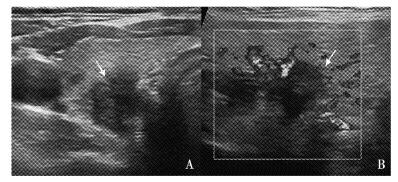

甲状腺结节的超声诊断及治疗